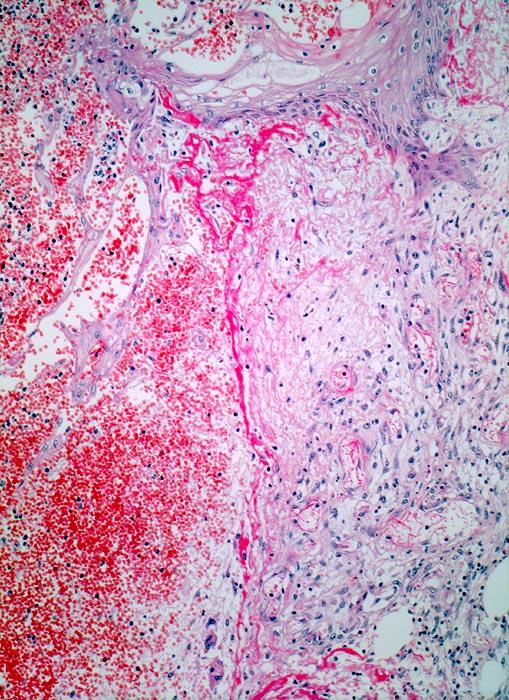

• Erste Phase (Exsudative Phase): Blutstillung durch Thrombozytenaggregation und Aktivierung des Gerinnungssystems. Ödembildung durch Freisetzung vasoaktiver Substanzen, gesteigerte Gefäßpermeabilität und verstärkte Exsudation von Blutplasma. Wäßriges Milieu mit örtlicher Azidose (Förderung von Zellteilung und Abbauprozessen, mechanische Reinigung der Wunde durch Ausschwemmen von Schmutz, Gewebetrümmern und Keimen). Phagozytose und Proteolyse von Keimen.

• Zweite Phase: Aufbau von Granulationsgewebe (= zell- und gefäßreiches Bindegewebe). Die Kapillarisierung (Neovaskularisation) durch Einsprossen von Blutgefäßen (Gefäßbäumchen sind als hellrote, glänzende Körnchen im Wundgrund sichtbar) sorgt für ausreichende Ernährung des Gewebes. Die Kollagensynthese durch eingewanderte Fibroblasten benötigt Vitamin C und Sauerstoff.

Morphologische Merkmale:

• Schlitzförmiger, bis in die Subkutis reichender Hautdefekt.

• Neugebildete Epidermis bedeckt im oberen intradermalen Anteil des Wundspaltes teilweise den Gewebsdefekt.

• Daran angrenzender Wundspalt im Bereich des subkutanen Fettgewebes mit Fibrinauflagerungen und ödematösem zellarmem Granulationsgewebe.

• An der Basis des Präparates Auseinanderklaffen des Wundspalts wegen grösserem Blutkoagel (verursacht Wundheilungsstörung).